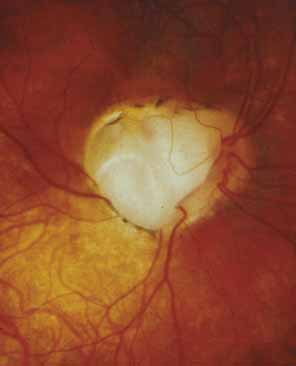

Complex microphthalmia is often associated with uveal colobomas. In the most common use of the term, “coloboma” refers to a defect in the iris, retina/uvea, and/or optic nerve as a result of faulty closure of the embryonic fissure at the 7- to 20-mm stage of development. Colobomas tend to be inferonasal, which is the normal position of the embryonic fissure (Fig. 1). The term “coloboma” has also been applied to other anomalies of the optic nerve, the macula, and the uveal tract that are not related to faulty closure of the embryonic fissure. This loose use of terminology creates unnecessary confusion when describing a syndrome. Hornby et al. found in their series that 72 of 185 eyes with coloboma also were microphthalmic and 71 of those 72 had microcornea.65 Thus, not every patient with microphthalmia has coloboma and not every patient with coloboma has microphthalmia. Microphthalmia has been postulated to arise from faulty development of the secondary vitreous and, hence, not enough pressure needed for prenatal eye growth.66

|